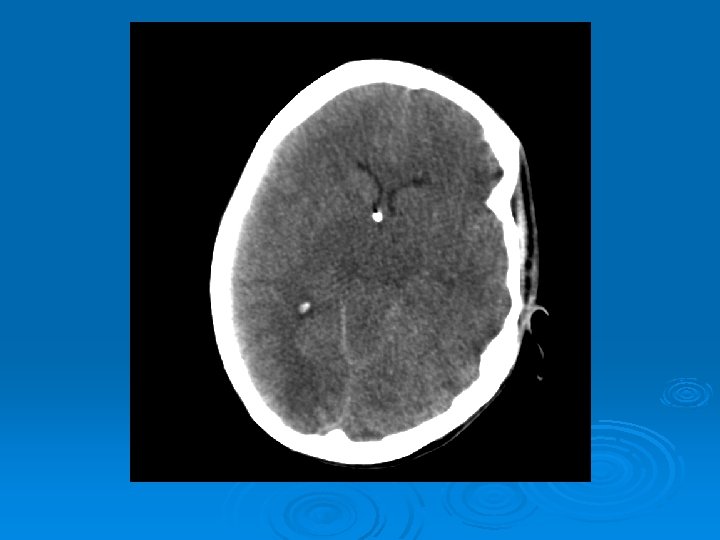

Course: Ø 3 PM, RN noticed anisocoria and L pupil non-reactive. Ø Neurology STAT dose mannitol and w/ dilantin. Ø Pt went for stat head Ct:

CT head 2/11/07 Ø A right frontal ventriculostomy catheter Ø Diffuse sulcal effacement with thickening of the cortex. Ø Loss of gray-white differentiation and hypodensity in the left parietooccipital region. Ø There is diffuse hypodensity of the cerebellum and brainstem. Ø Ø Ø The basilar cisterns are nearly completely effaced. Ø Impression: Ø Worsened diffuse cerebral edema The lateral ventricles are smaller

Course: Ø Neurosurgery saw pt: on exam she had lost cough, gag reflexes, corneal reflexes, she had flexed RUE, semipurposeful with bilateral extended LE. Ø Concern for herniation: placed Ø ICP 35 -40 10 th-11 th EVD